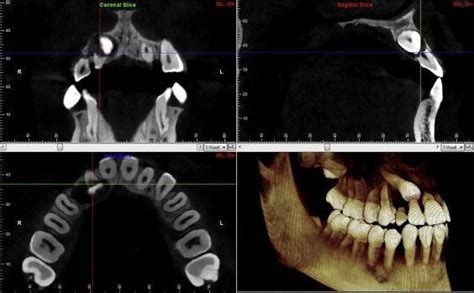

Maxillary Canine Impaction: Root Resorption and CBCT Diagnosis